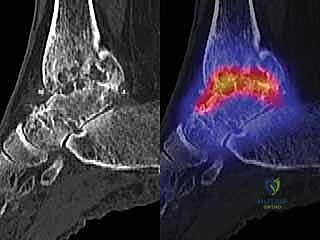

* التصوير الشعاعي المتقدم: صور أشعة سينية (X-rays) في وضعية الوقوف (تحميل الوزن) لتقييم المحور الميكانيكي للساق والقدم.

* الأشعة المقطعية (CT Scan): للحصول على رؤية ثلاثية الأبعاد للعظام، تقييم حجم التكيسات العظمية (إن وجدت)، والتخطيط الدقيق لحجم المكونات المعدنية.